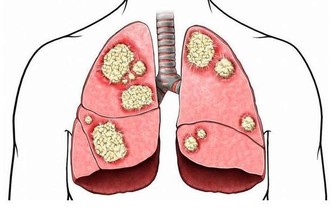

濫用抗生素使越來越多的細菌產生了耐藥,一些原來使用過的很有效的抗生素在對同樣的人及同樣的疾病漸漸失去了效力,使用後感染引起的發熱不退,感染灶也不見縮小或消退。為此,專家們不得不絞盡腦汁,去研究發現對付耐藥菌的新型抗生素。讓人煩惱的是,新抗生素的發現速度遠遠還趕不上細菌產生耐藥的速度,而且耐藥細菌的毒力變得越來越強,越來越難以處置。為了對付細菌的耐藥性,醫生們不得不同時使用多種抗生素,聯合使用對付一個病人正面臨的複雜的感染,當然在殺死有害細菌的同時,一些脆弱的益生菌也會同時被“殺死”,導致機體菌群紊亂,降低機體的抵抗力。

所謂的超級細菌(superbug)不是特指某一種細菌,而是泛指那些對多種抗生素具有耐藥性的細菌,它的準確稱呼應該是“多重耐藥性細菌”。這類細菌能對抗生素有強大的抵抗作用,能逃避被殺滅的危險。